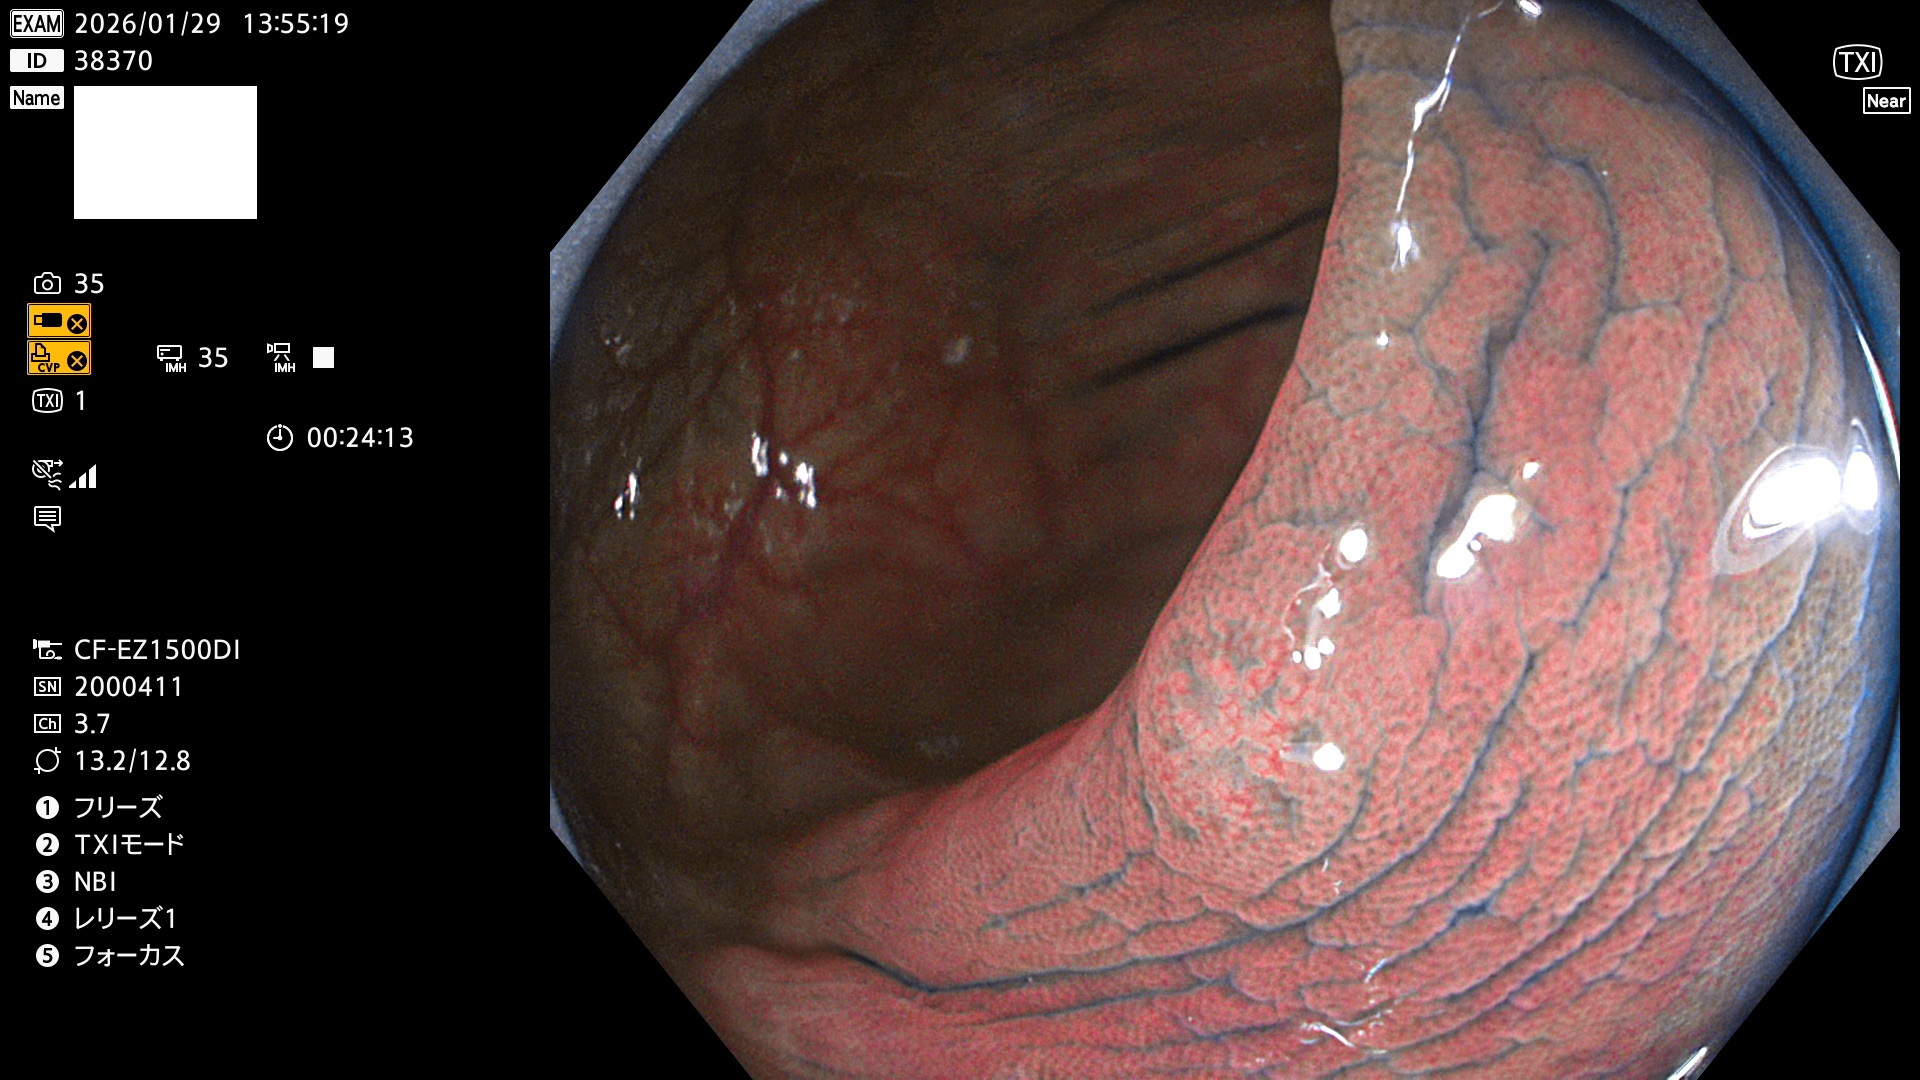

完全に平坦な物をUb、陥凹している物をUcと呼びます。Ubは認識が困難で、Ucはびらん(炎症)と紛らわしいために見落とされやすく、「内視鏡後・大腸癌」の原因になります。

毎週の検査(木・金・土・日)に発見されたUbとUc型・腺腫を、その週の日曜の夜にUPし1週間、提示します。

2026年1月29日〜2月1日の4日間(40件)10個 (Uc_ADR=10個/40人=25%)